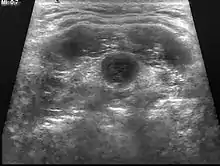

Ultrasound image of thyroglossal duct cyst

Diagnosis of a thyroglossal duct cyst requires a medical professional, and is usually done by a physical examination. It is important to identify whether or not the thyroglossal cyst contains any thyroid tissue, as it can define the degree of cyst that is being dealt with.[1]

UltrasoundImage capture of the degree of mass and its surrounding tissues.